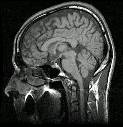

What type of image is it? MRI scans (T1 or T2 weighted)

Which plane the image is in? axial, sagittal or coronal (see

pictures below)

Saggital scan |